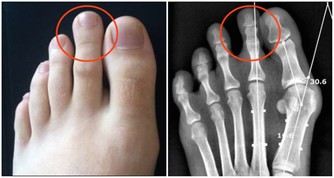

2.預防心血管疾病。大蒜能夠防止脂肪和膽固醇在血管中沉積,幫助血管舒張,維持血管健康,所以它有抑制血栓,預防心血管病的作用。